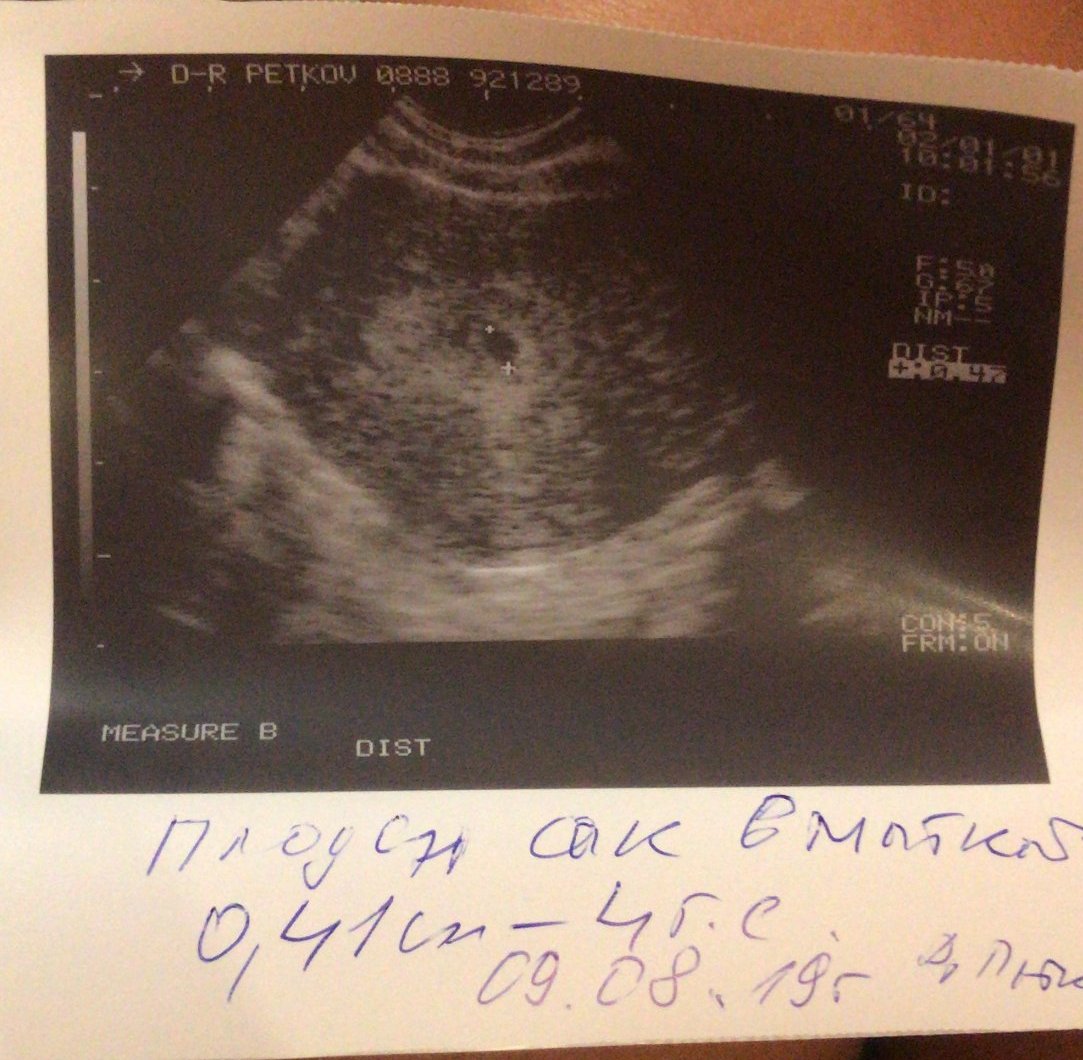

Здравейте мамита,от скоро съм тук и искам да споделя радостта си с вас,защото нали не можело да се казва на никой до 3тия месец,иначе така искам да кажа на всички